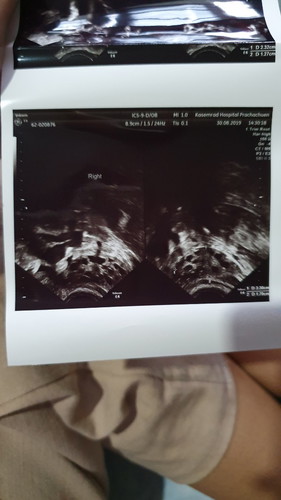

ตอนนี้ท้องได้ 11 w 2 d แล้วค่ะแต่เป็นซีสต์ที่รังไข่ด้วย

ทราบก็ต้องไปตรวจ ตอนนั้นท้องได้ 7 w ค่ะ หมอก็ตรวจส่องกล้องไปเจอซีสต์ที่รังไข่ ตอนนี้ก็ไม่ค่อยสบายใจเครียด แต่ก็พยายามไม่เครียดอารมณ์ดีๆไว้ กลัวลูกเครียดตามค่ะ แม่บ้านไหนเจอภาวะแบบนี้บ้างค่ะมีแนวทางปฎิบัติตัวยังไงบ้างค่ะ